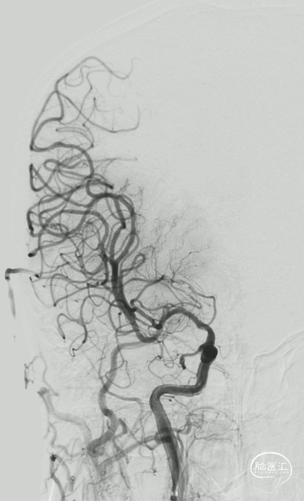

右侧大脑中动脉起始部闭塞,左侧前交通开放,左侧大脑前动脉通过软膜支代偿,大脑后动脉通过软膜支代偿,侧支代偿可,考虑粥样硬化合并急性闭塞的可能。

释放Syphonet®取栓支架 5*35mm,造影显示:支架释放效应可疑阳性。

取栓后造影,M1再通,局部狭窄可能,前向血流延迟。

再次释放Syphonet®取栓支架 5*35mm,造影显示:支架释放效应阳性。

球扩后造影:狭窄明显改善,前向血流明显好转,未见血栓征象,球囊部分回收支架,撤出。

观察15min,未见弹性回缩,正侧位造影。